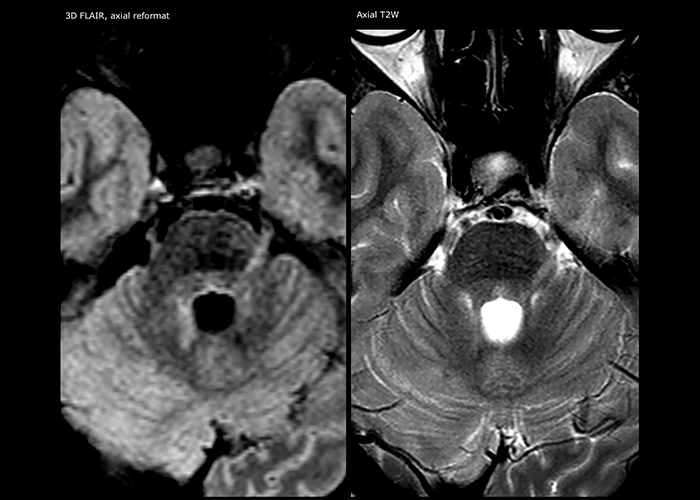

When multiple sclerosis (MS) is suspected, clinicians need a diagnosis early on, so treatment can begin as soon as possible. “A challenge for imaging is that MS lesions in the brain and spine may be very small,” says Dr. Savatovsky. “We need precise imaging to tell exactly where the lesion is, so we need high quality, very high resolution images, preferably in 3D[1]. We need to know if a high T2 signal intensity is suggestive of MS or just aspecific. And we want to visualize active lesions very well.”

“Ingenia 3.0T provides us very good image quality with high SNR, even if we push the resolution. For example, in FLAIR images we may have an isotropic resolution of 0.9 mm. Ingenia allows us to use 3D T1 TSE with BrainView, which has a better sensitivity than 2D spin echo imaging[2] and 3D gradient echo imaging. Ingenia also provides highly reproducible exams, which is important in MS imaging so that follow-up exams at different time points are done the same way.”

For MS imaging in the brain, Dr. Savatovsky uses 3D FLAIR as the basic sequence to visualize the lesions and assess the situation and lesion load. “We count the lesions in each location to determine if the criteria of the disease are fulfilled. We use a T2-weighted sequence because our neurologists are used to it. We compare the lesion load on FLAIR with a 3D T1 post-contrast sequence to help us determine whether lesions are old or new. We typically administer the contrast before the patient enters the machine because it shortens the examination time and allows to visualize active lesions that tend to be more visible after several minutes. When a differential diagnosis is difficult, we add sequences such as susceptibility imaging, because some focal MS lesions have a small vein in the center[3].”